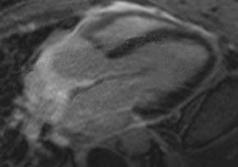

Gastric GIST shows an intermediate pattern of enhancement, while small bowel GIST shows marked arterial phase enhancement. ‘Tumour vessel’ sign, a feature of small bowel GIST due to early venous return and prominence of the draining vein, helps in tracing the origin of the tumour. A nodule within the mass is a sign of recurrence.1 Treatment of choice for resectable GIST is surgery, although neoadjuvant imatinib is given to reduce the tumour size, and postsurgery imatinib is administered to prevent recurrence of the disease for at least 3 years. In case of metastasis or recurrence, imatinib is a first line drug.4,10,11,20

CONCLUSION

Although CT is the modality of choice for GIST, it is imperative for a radiologist to be wellacquainted with various other non-cross section imaging, such as radiographs, small bowel series, and ultrasound, to increase the level of confidence in radiological diagnosis before histopathology and immunohistochemistry confirms it.

Creative Commons Attribution-Non Commercial 4.0 ● April 2024 ● Radiology 91 Case Report

References

1. Inoue A et al. Gastrointestinal stromal tumors: a comprehensive radiological review. Jpn J Radiol. 2022;40(11):1105-20.

2. Levy AD et al. Gastrointestinal stromal tumors: radiologic features with pathologic correlation. Radiographics. 2003;23(2):283304.